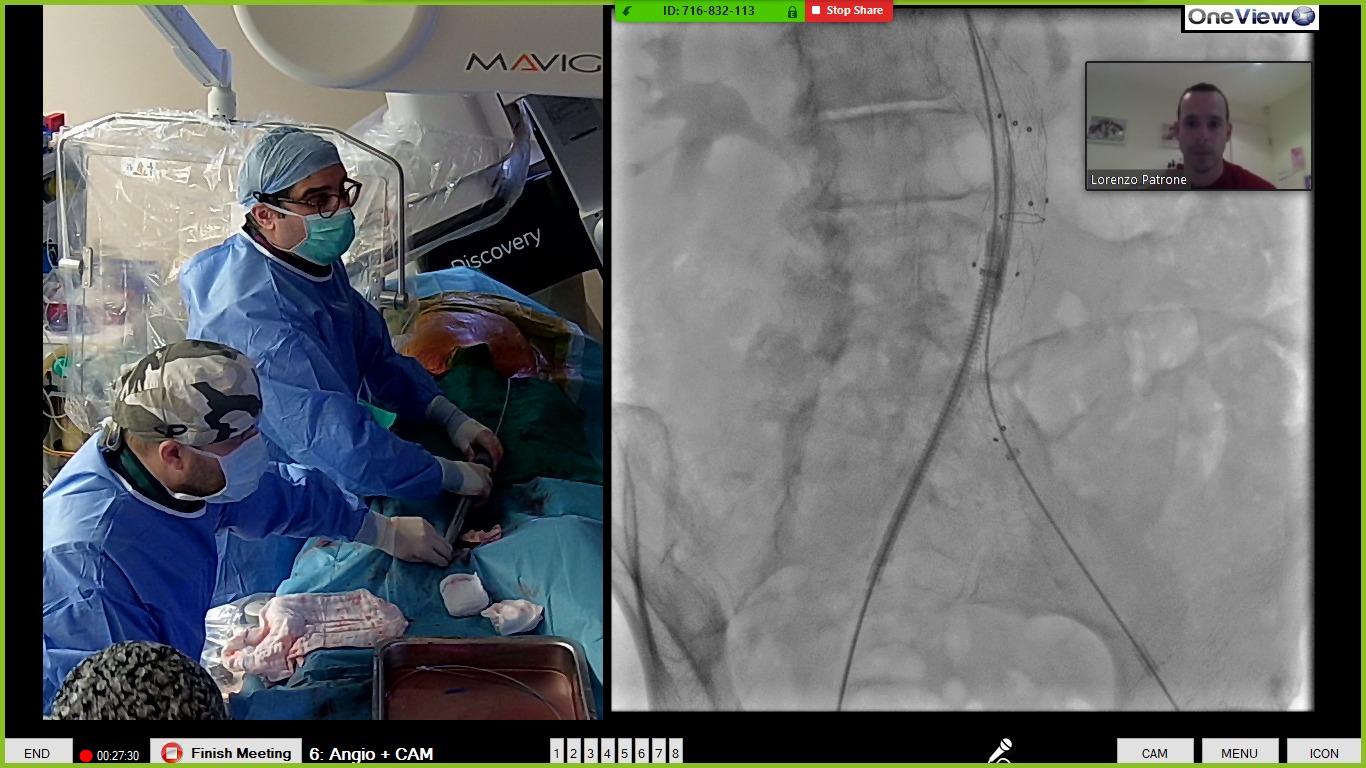

Ο Δρ. Μπίσδας σε ζωντανή αναμετάδοση από το Υβριδικό Χειρουργείο του Ιατρικού Κέντρου Αθηνών εκπαιδεύει ως proctor πολλών εταιρειών αγγειοχειρουργούς και επεμβατικούς ακτινολόγους ανά την υφήλιο σε πολύπλοκες αορτικές επεμβάσεις

Η αγγειοχειρουργική ομάδα στο υβριδικό χειρουργείο ΠΡΟΜΗΘΕΑΣ. Από αριστερά προς τα δεξιά: Δρ. Ηλίας Κανελλόπουλος (Αναισθησιολόγος), Δρ. Νικόλαος Πατέλης (Αγγειοχειρουργός), Αν. Καθηγητής Δρ. Θεοδόσιος Μπίσδας (Αγγειοχειρουργός), Δρ. Ουρανία Γαλανοπούλου (Αναισθησιολόγος).